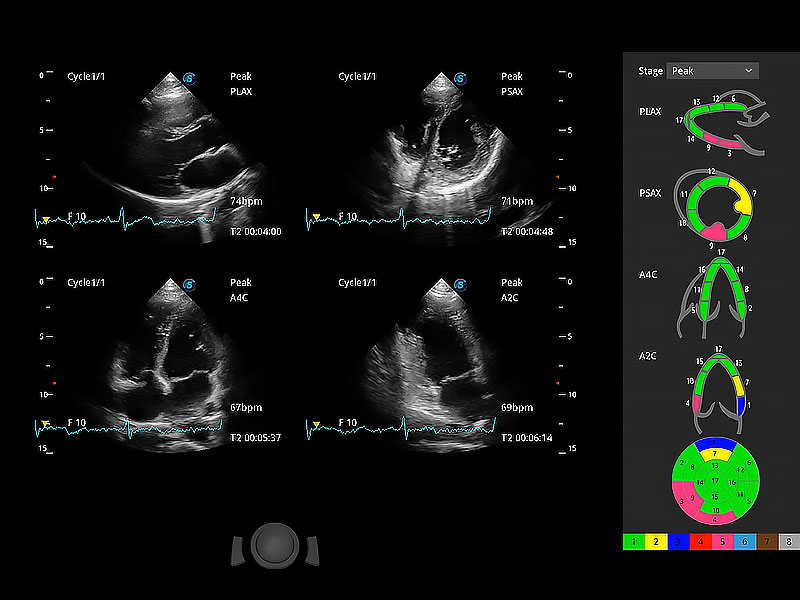

ProPet 80 配備了豐富的心臟探頭群、先進的成像技術(shù)和專業(yè)的心臟測量工具,可幫助動物醫(yī)生為不同體型和生理結(jié)構(gòu)的動物提供心臟和心肌功能的全面評估。

通過心肌識別技術(shù)與二維斑點追蹤技術(shù)相結(jié)合,對心臟的超聲圖像進行量化分析。計算心肌17個節(jié)段的應(yīng)變、應(yīng)變率、速度、位移等,并通過牛眼圖的形式進行呈現(xiàn)。

通過360度任意調(diào)節(jié)3條M型取樣線,在同一心動周期上觀察心臟不同位置的運動曲線,得到準確的心功能測量數(shù)據(jù),有效評估心肌運動及左心室功能。

具備多種協(xié)議可選,同時支持17階段劃分法和專業(yè)的SE報告。

能夠基于左心室壁追蹤和辛普森法,自動計算射血分數(shù),支持多個可移動點描跡,與手動測量相比,極大節(jié)省了動物醫(yī)生的時間和精力。